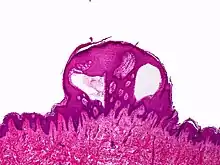

| Lymphangioma circumscriptum; only stratum papillare is affected. | |

A biopsy of the affected skin and histological examination under the microscope is necessary to diagnose lymphangioma circumscriptum.